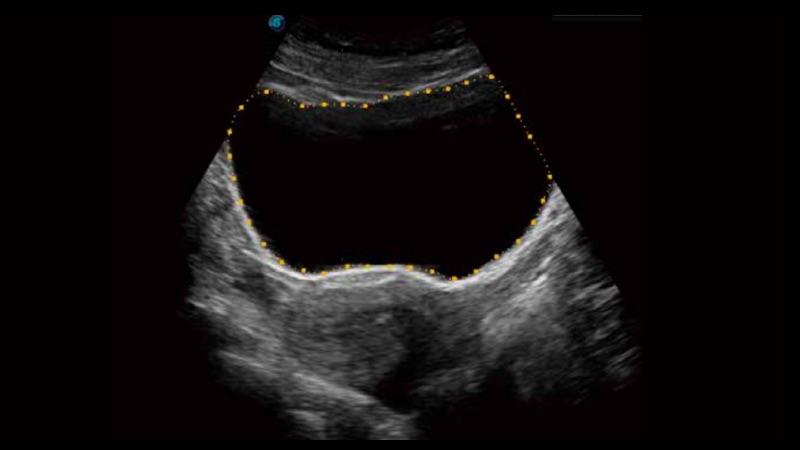

膀胱自动测量,一键式膀胱壁追踪和容量测量可有效提供更精确的轮廓和结果,不受膀胱形状和大小的影响。